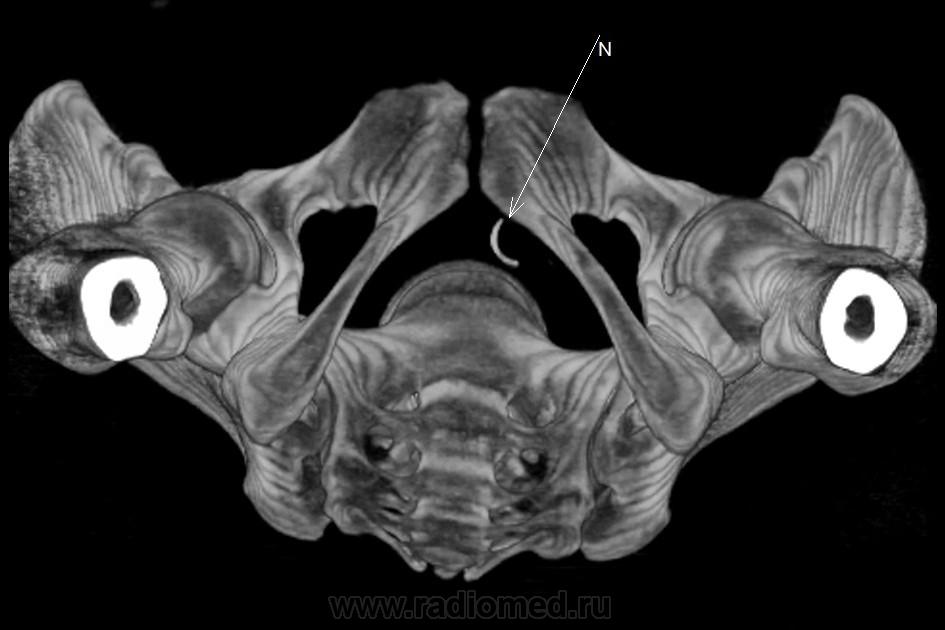

Инородное тело. Хирургическая игла.

Хирургическая игла, которую оставили гинекологи.

Да, гинекологи сами почуяли неладное и отправили пациентку на исследование. Операция была по поводу кисты левой бартолиневой железы. Со слов пациентки, ей до этого делали УЗИ, но ничего не обнаружили. Расположена она в толще большой половой губы, в преддверии влагалища.